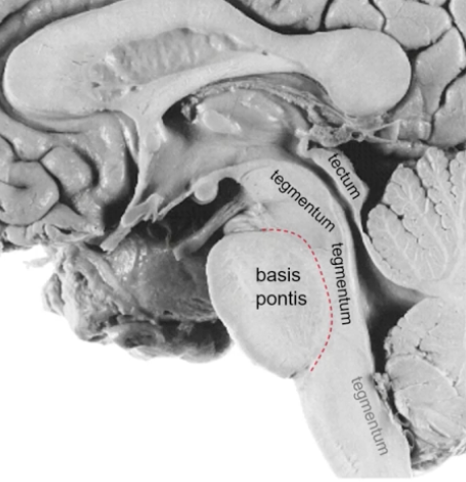

A

midbrain

pons